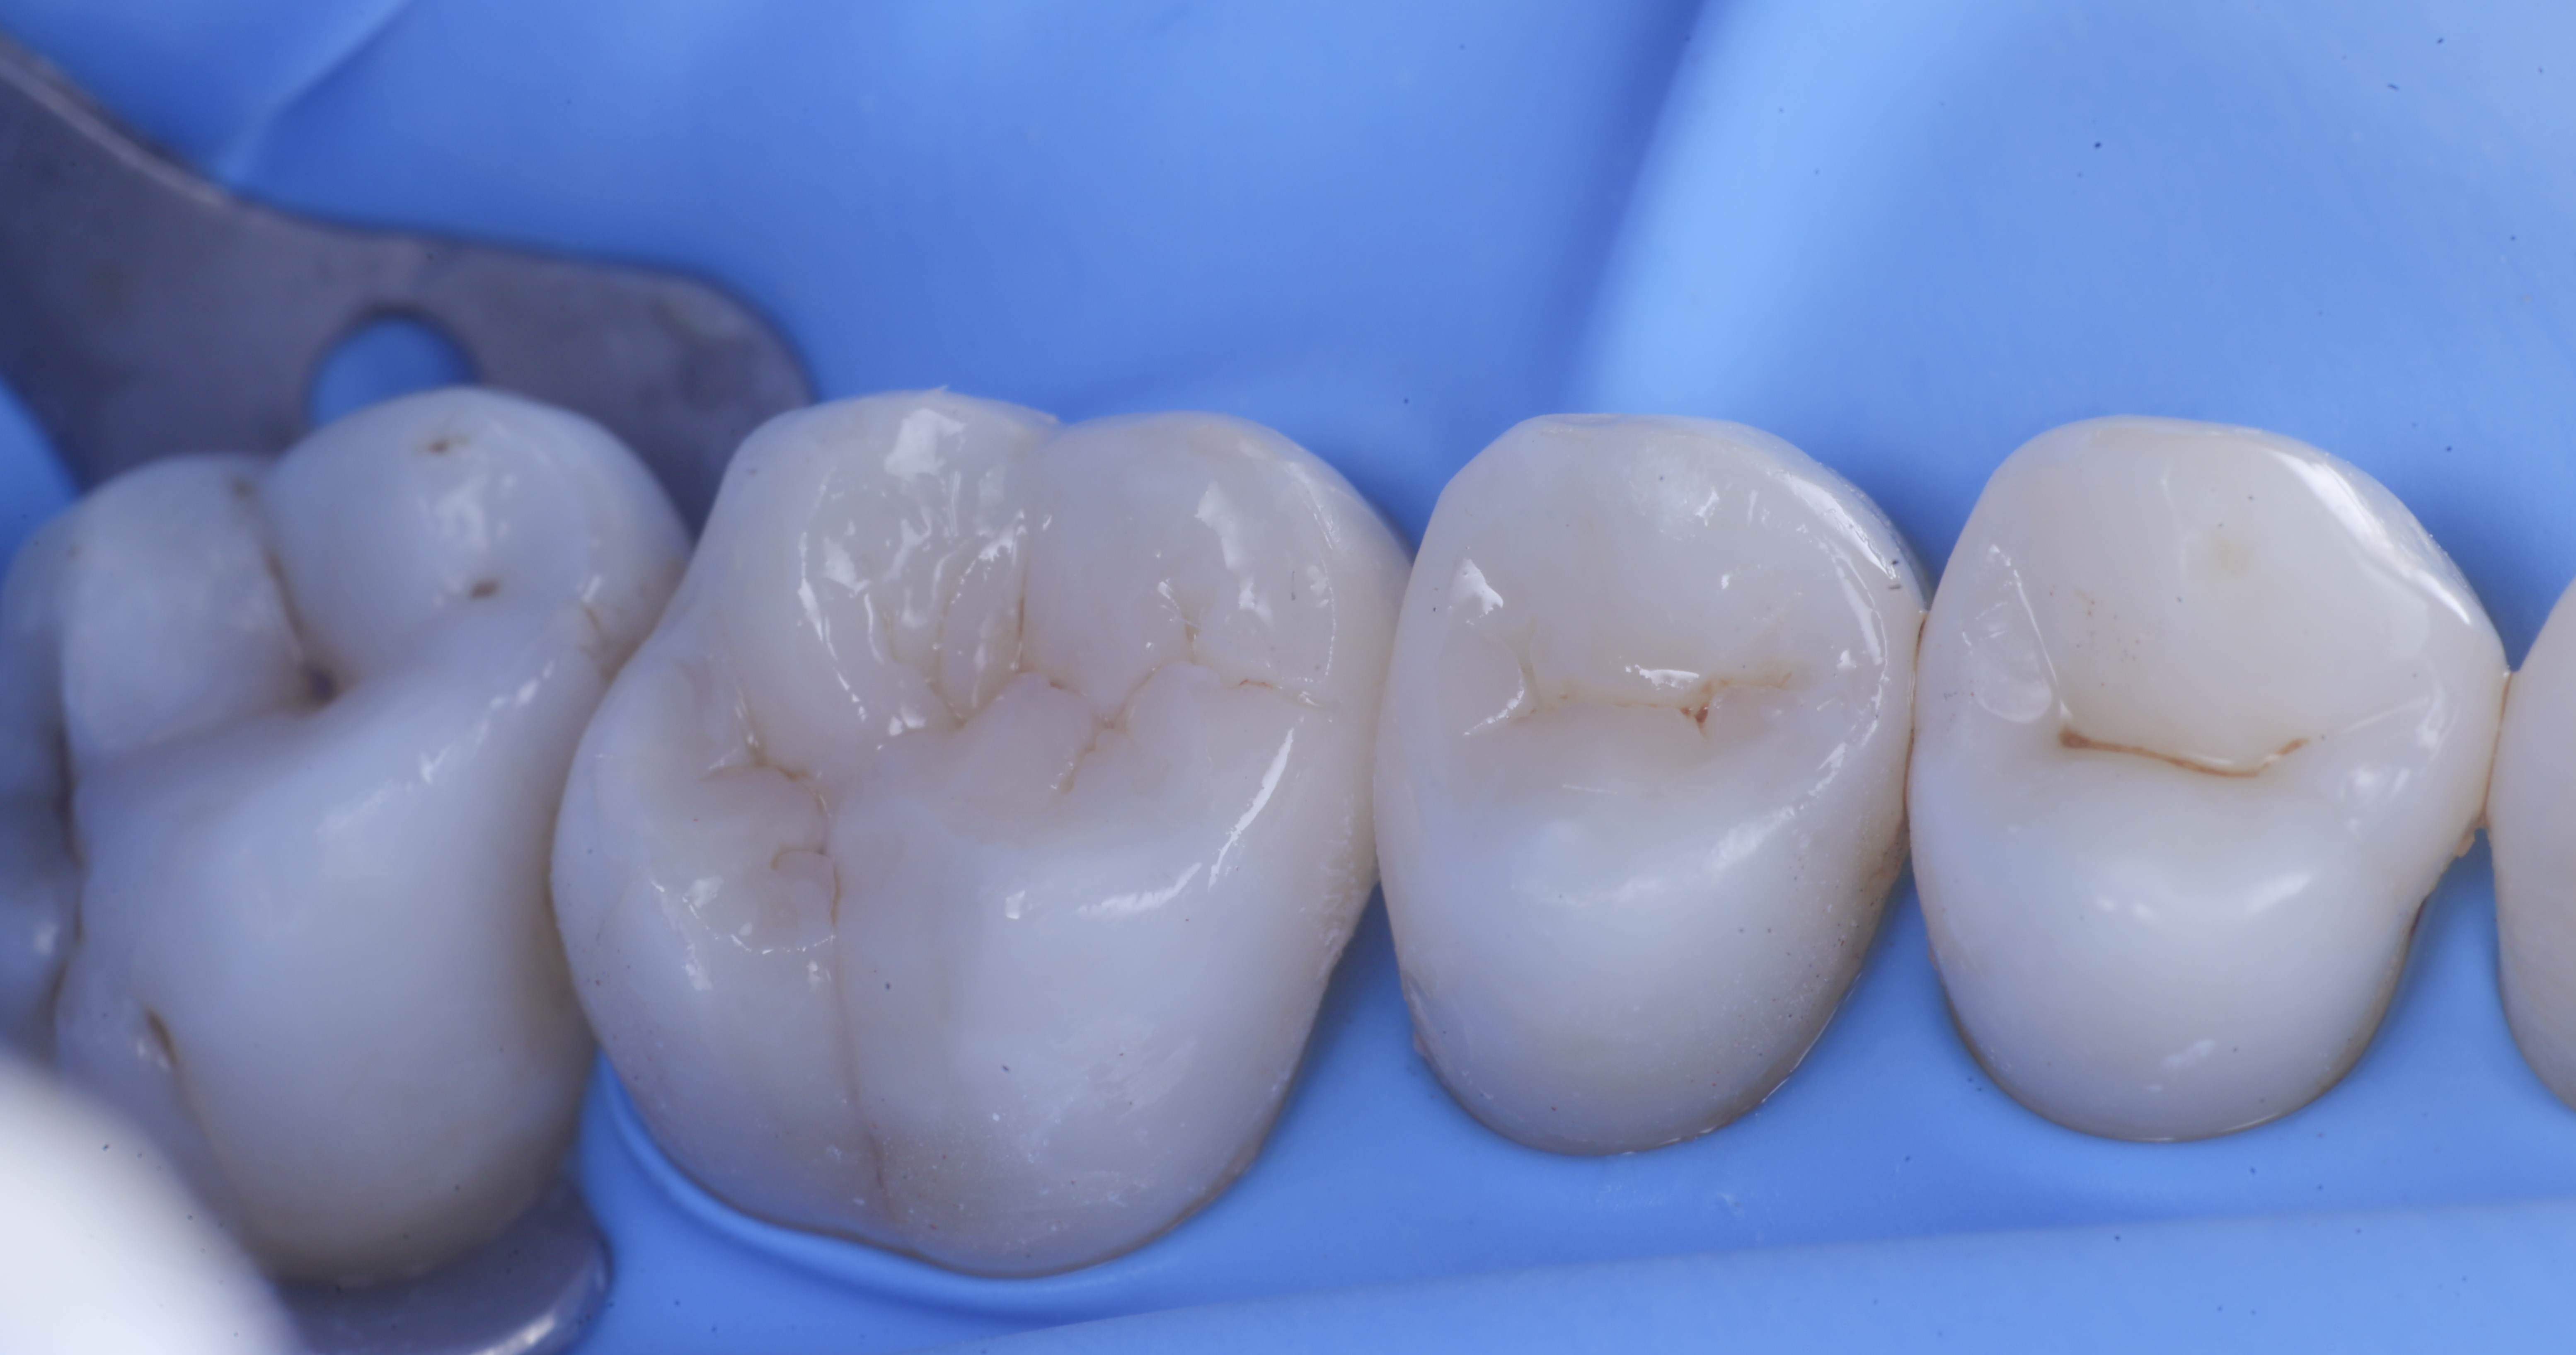

foto 6 Aspetto occlusale delle pareti interprossimali appena create

foto 7 Aspetto vestibolare delle pareti interprossimali appena create

Trasformate le cavita da II classi a I classi si procede con la classica modellazione cuspide per cuspide, sfruttando le caratteristiche meccaniche e anche estetiche dei materiali compositi bulk.